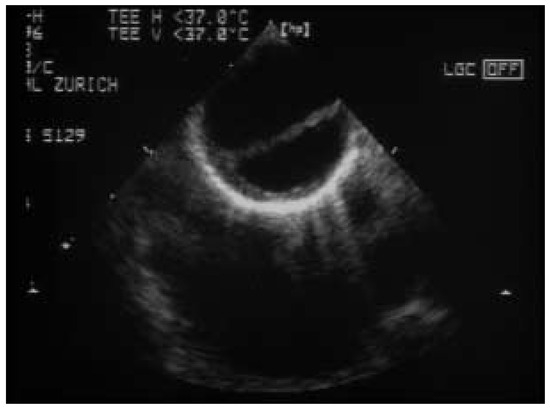

Une patiente de 31 ans souffrant d’une cardiopathie congénitale consulte car elle souhaite une grossesse [...]